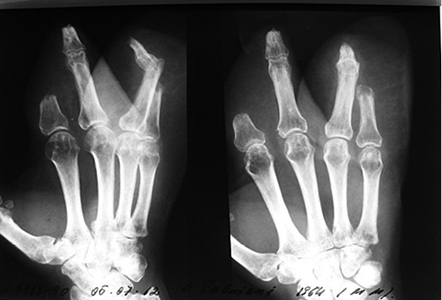

3 pav.

4 pav.

Priekinė ir šoninė kairės plaštakos rentgenograma. Stebimi II ir V pirštų kauliniai defektai per proksimalinį interfalanginį sąnarį (3 ir 4 pav.)